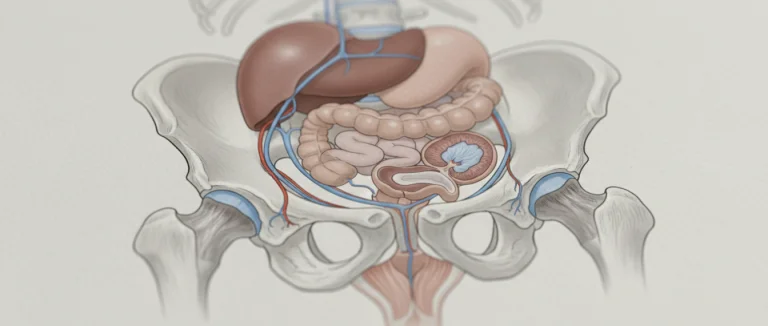

печенью

пищеварительной

поджелудочной железы

простата

Простата

Простатa